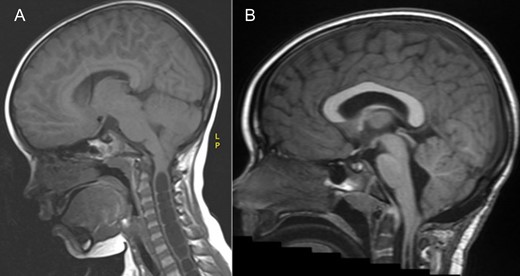

MRI brain demonstrating the chiari 1 malformation. Pre-op sagittal T1 showing cerebellar tonsillar descent of 9 mm below the foramen magnum (A) and at 3 years post op showing adequate hind brain decompression (B).

At 1 year follow-up, his foot drop had gradually improved. He was able to walk on his tip toes and heels. By 2 years follow-up, his foot drop had completely resolved and ankle dorsiflexion was 5/5 on the right. An MRI at three years post op demonstrated a good foramen magnum decompression (Fig. 1) and significant improvements in the syrinx (Fig. 2), however not complete resolution.